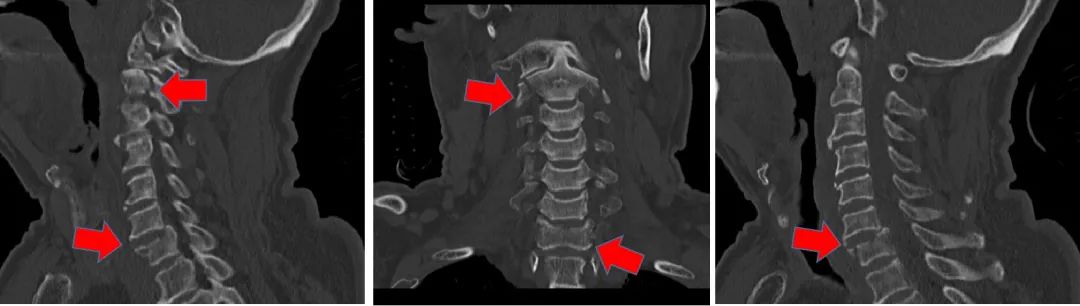

CT可见多处颈胸椎骨折

由于老人年事已高,发生骨折的位置又很棘手,加上有明确的脊髓损伤,一家人辗转多个医院都没能被收治,直至来到清华长庚神经外科。孙振兴医师接诊后,和科室医生张培海、荆林凯讨论,一致认为如果不能将患者断掉的脊柱重新扶直、固定的话,他根本无法翻身活动,随时有二次脊髓损伤加重的风险,届时面临的就是高位截瘫。而这个年纪的高位截瘫对老人意味着什么?神外团队决定挑战一把!

风险最大的地方仍为枢椎,如果置钉固定时外侧穿多了,伤到枢椎侧方供应大脑25%血液的椎动脉,就会大出血;如果里侧穿多了就会损伤脊髓,术中就会造成高位截瘫。每个位置置钉的机会只有一次,在术中CT和神经导航系统的引导下,孙振兴团队凭借丰富的经验,准确果断操作,经过7个多小时奋战,成功为李老完成了脊柱多处骨折复位固定手术。